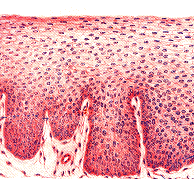

The images below show a magnified cross section of the lining of the oral cavity and the throat. On the left is a normal example, and on the right is an example of squamous cell carcinoma. You can that the cancer is much darker in its coloration (the biopsy specimens are all colored with special stains that make identification easier). The cancer also shows invasion into the underlying tissue layers, while the normal tissue has an orderly appearance. The pathologists who make the diagnosis rely on these and many other clues to distinguish normal tissue from cancerous growths.

Normal cells

Squamous Cell Carcinoma

Normal cells Squamous cell carcinoma